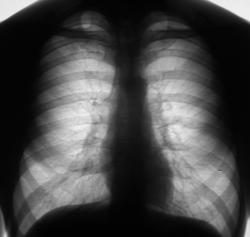

Флюорограмма 2008 г.

3.F-graf..JPG

В 2008 году пациент был взят на контроль и был вызван на дообследование, но "вдруг исчез" из населенного пункта. Но в этом году, а именно сегодня пациента удалось дообследовать.

Инфильтративный туберкулёз справа

инфильтративный туберкулёз.